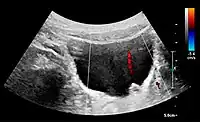

Doppler ultrasound (US) of a normal adult kidney with the estimation of the systolic velocity (Vs), the diastolic velocity (Vd), acceleration time (AoAT), systolic acceleration (Ao Accel) and resistive index (RI). Red and blue colors in the color box represent flow towards and away from the transducer, respectively. The specrogram below the B-mode image shows flow velocity (m/s) against time (s) obtained within the range gate. The small flash icons on the spectrogram represent initiation of the flow measurement.[1]